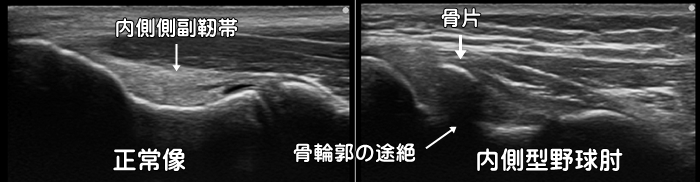

野球肘・離断性骨軟骨炎

野球をしていて肘の内側や外側に痛みを感じた場合、内側型・外側型の野球肘を疑います。自覚症状は圧痛・外反ストレス痛・可動域制限です。ただし外側型の野球肘は初期では自覚症状に乏しく、症状が現れた頃にはかなり進行して手術を必要とすることもある為、エコーによる早期発見が重要です。